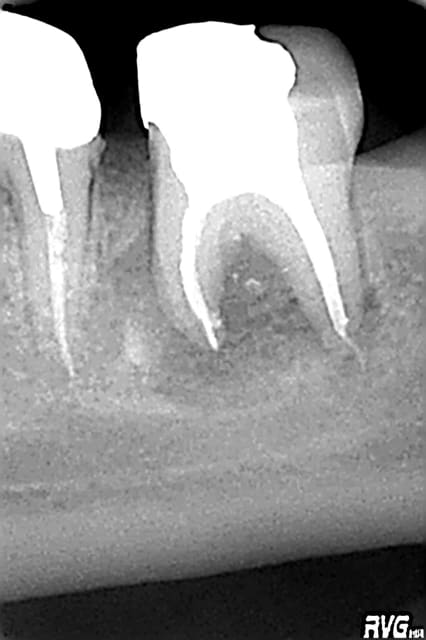

Est ce un fait exprès? Mais depuis mon retour, presque toute ma pratique tourne autour des reprises ENDO, et là, il faut que j'avoue toute l'admiration que j'ai pour les endodontistes exclusifs, c'est tout bonnement éreintant cette discipline, surtout lorsqu'on tombe sur des os!

Est-ce un fruit du hasard, mais les interventions que j'ai négociées représentent pratiquement tous les cas de figure qu'a traité Stéphane:

- fausse route bouchée au MTA

-instrument fracturé impossible à retirer, je suis passée à côté et je l'ai noyé dans la gutta chaude.

Et tout de même quelques racines domptées sans trop de difficultés!